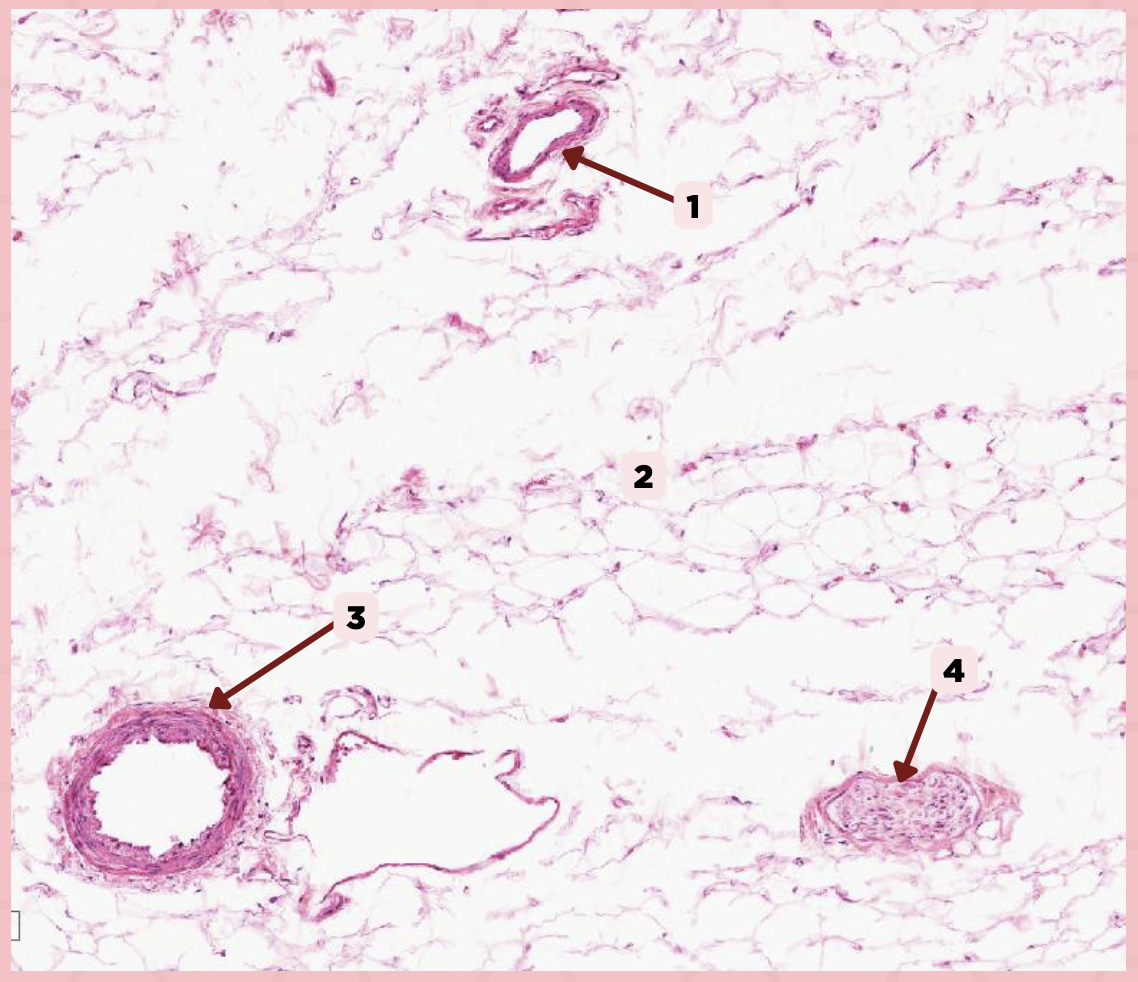

Vein

Identify the structure labeled as 1.

Hypodermis

Identify the structure labeled as 2.

Artery

Identify the structure labeled as 3.

Nerve

Identify the structure labeled as 4.

Cheek

Identify the specimen.